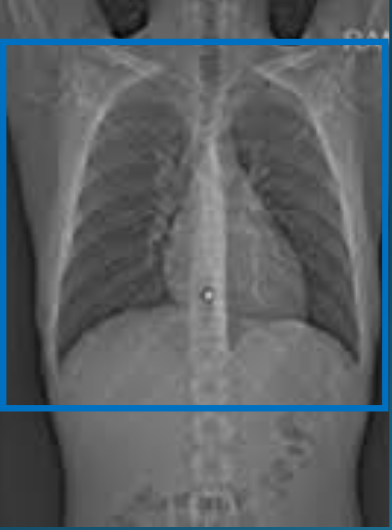

Visão geral do posicionamento para Tórax (Fonte: Wikimedia Commons)

Planejamento TC Tórax (Fonte: Wikimedia Commons)